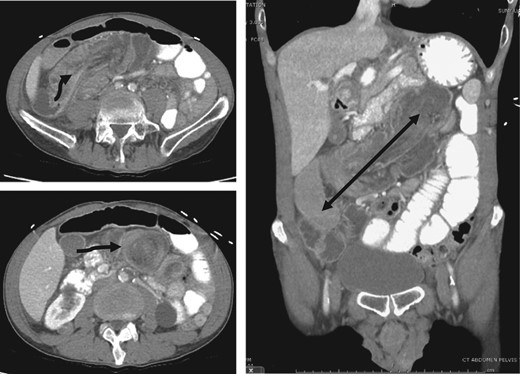

Top left: origin (arrow) of invagination in the right lower quadrant. Bottom left: the classic ‘target sign’ (arrow). (Right) Coronal demonstrating the extent of intussusception.